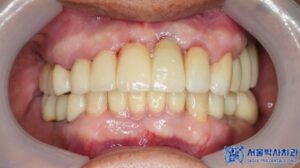

환자분께서는 최종 보철을 장착한 후,

음식을 씹는 느낌도 자연스럽고

앞니가 예쁘게 만들어져 매우

만족스럽다고 하셨으며,

처음 내원하셨을 때와 비교하면

얼굴 표정도 한결 밝아지셨습니다.

무절개 방식 덕분에 부기도 거의 없었고,

임시 치아를 바로 해줘서 불편함이

없었다고 하셨습니다.